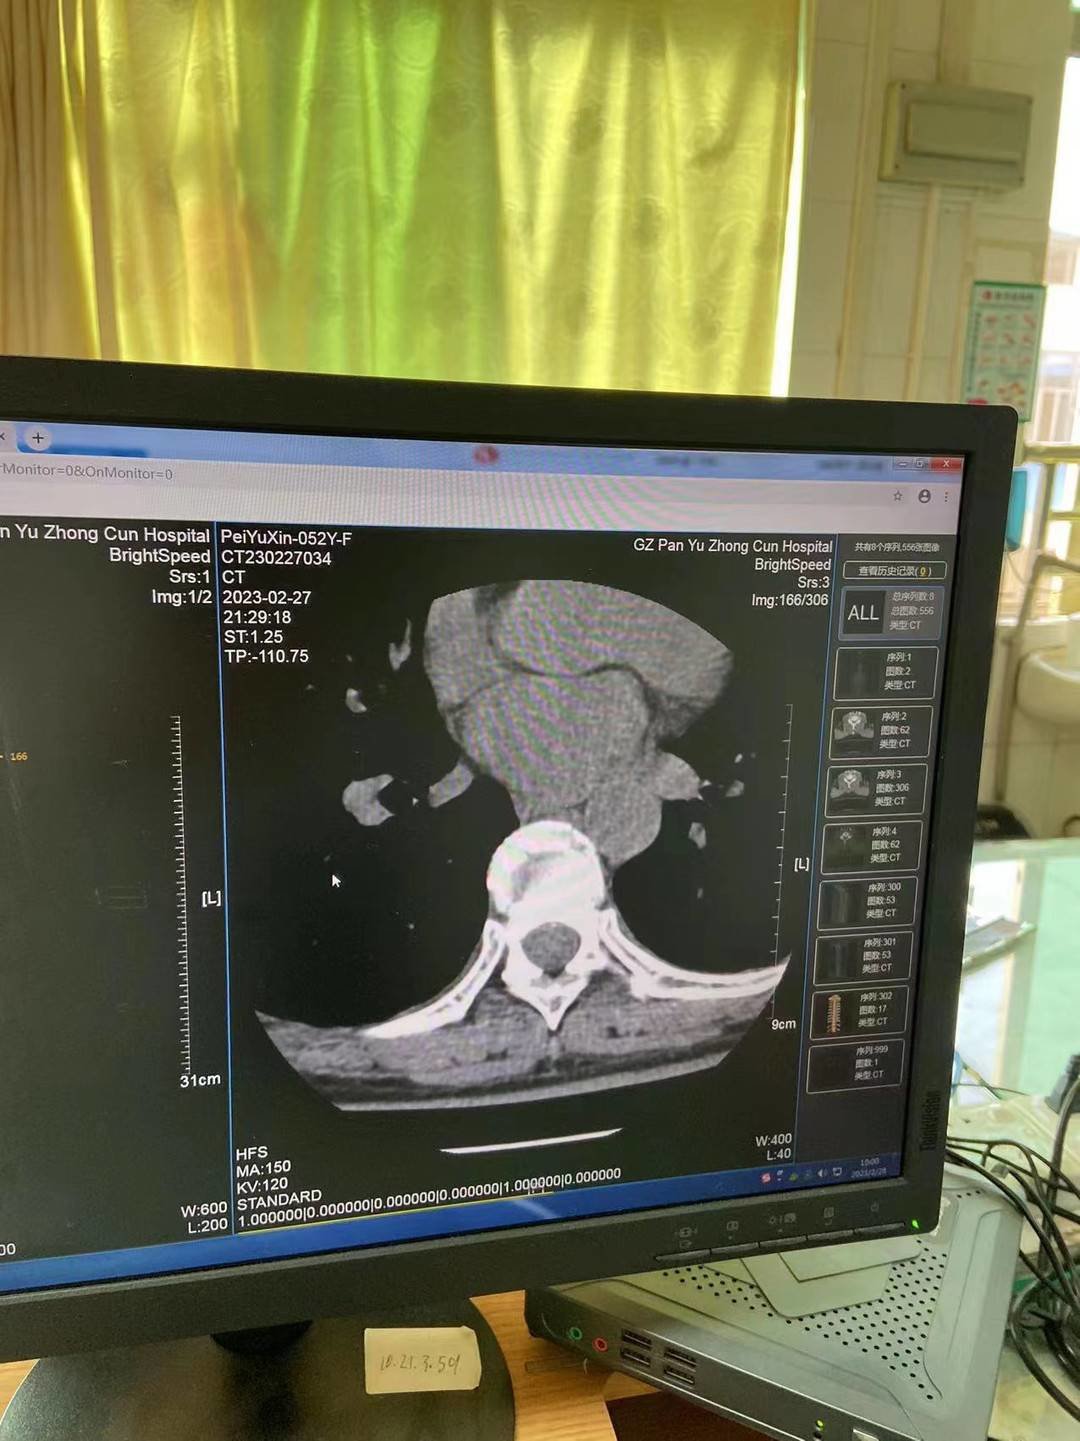

医院出示检查报告

裴谕新向记者提供的CT检查报告显示,胸8椎体明显变扁塌陷,压缩约1/3,骨碎片向周围移位,胸8锥体压缩性骨折。目前她仍然在医院接受治疗。